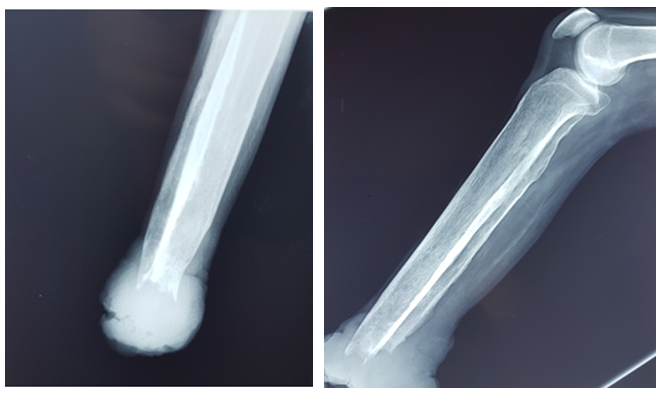

A 40-years-old man attended the dermatology department in Hassan II hospital in Fez with a 20years history of non-healing ulcer on the back foot. It wasn’t associated with pain. There was no history of diabetes mellitus, and he was a non-smoker. He was mobile and lived independently. The evolution was marked by the extension of the ulcer, and progressed to substance loose leading to spontaneous amputation of more than 1/3rd of the leg. Examination revealed an ulcerative budding stump of the leg (Figure 1). A biopsy was done, and the anatomy pathology revealed a verrucous spinocellular carcinoma. Leg radiography showed a complete destruction of the fibula and tibia and resorption of the remaining bones of the leg. An ultrasound of ganglionic areas and a thoraco-abdominal CT scan didn’t reveal any abnormalities (Figure2). After consultation with the traumatologist, the patient had undergone transtibial amputations with lymph node dissection. The anatomy pathology concluded to spinocellular carcinoma. The patient healed and is still alive 3years after the amputation. He didn’t present any similar lesions.

Figure 2 Bone destruction and resorption.